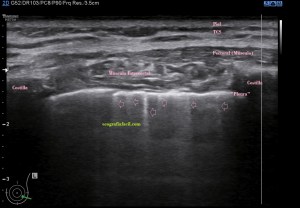

Era un nódulo hiperecogénico en el contexto de la tiroiditis en el estudio de una ecografía tiroidea.

Te enseño las imágenes, típicas de una exploración tiroidea de protocolo con semiología de tiroiditis.

De la imagen 1 a 7 el protocolo habitual, el estudio particular del nódulo con medidas y aplicación del doppler demuestra el aspecto típico del Caballero Blanco.

De la 8 a la 11 estudio con Doppler.

La imagen 12 y 13 están adquiridas con una sonda de 18 Mhz.

En la 14 un ganglio reactivo con medidas respetadas.

El el 15 tienes un vídeo de un corte axial de El Caballero Blanco.

Resumen de las imágenes que has visto en el caso de hoy:

1. Hipoecogenicidad del parénquima

2. Heteroecogenicidad

3. Múltiples nódulos hipoecoicos muy pequeños

4. Doppler Color y Doppler Power aumentado de tamaño en el nódulo

Este es el aspecto ecográfico descrito anteriormente de la patología que habitualmente puede albergar el nódulo del que trata hoy el post y que no es otra que la de la Tiroiditis de Hashimoto.

El Caballero blanco, recibe el nombre debido a su semiología hiperecogénica, homogénea y solitaria circunscrito en la patología referida con anterioridad, puede aparecer en esta patología de forma benigna o degenerar en otro tipo de patología a formas malignas como el linfoma tiroideo.